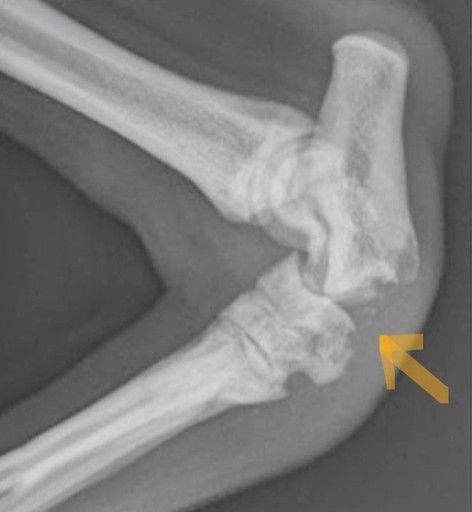

X-rays are recommended to rule out fractures and evaluate surrounding structures, although the diagnosis is often made based on examination findings alone.

Partial Achilles Rupture

Complete Achilles Rupture

X-ray changes with Partial and Complete Ruptures